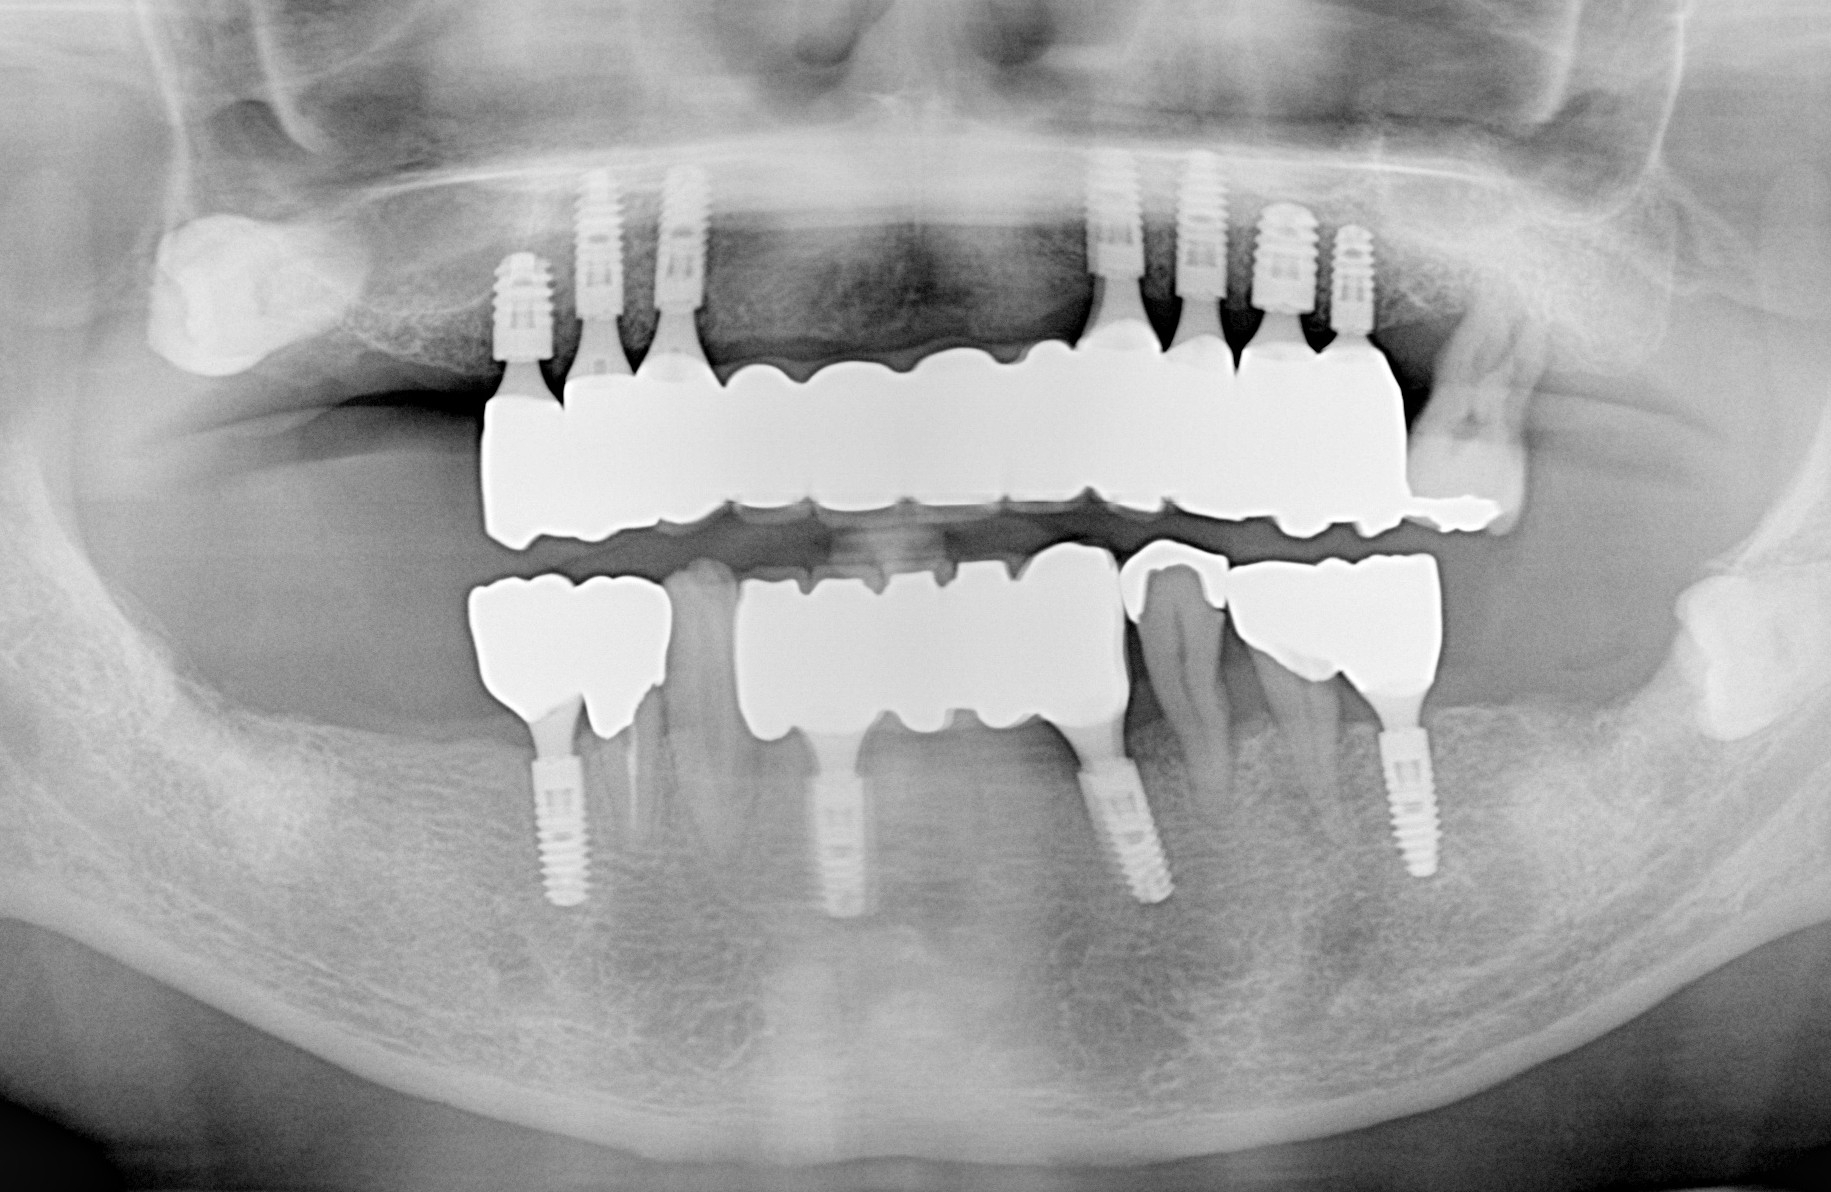

レントゲン画像

下顎の無歯顎に4本のインプラントで固定式ブリッジ

下顎の無歯顎に4本のインプラントで固定式ブリッジした症例

治療の解説 60歳代男性の下顎の無歯顎に4本のインプラントで固定式ブリッジした症例です。下顎の総入れ歯が合わないとのことで来院なさいました。固定性の義歯をご希望でしたので、インプラント治療に関する手術、上部構造、メインテ […]

総入れ歯と部分義歯をインプラント治療でしっかり咬める固定式の歯に改善した症例

治療の解説 60歳代 男性、上顎に現在使用中の総入れ歯よりもしっかり咬める固定式の歯にするため、インプラントを合計7本埋入し12本分の歯を入れた症例及び、下顎の部分義歯を固定式のインプラントにするため左右大臼歯部に1本ず […]

60歳代 女性、上顎の取り外し式の義歯を固定式のインプラントブリッジにするためインプラントを合計8本埋入し12本分の歯を入れた症例及び、下顎の前歯部の不適合ブリッジを抜去しインプラントを合計7本埋入し11本分の歯を入れた […]